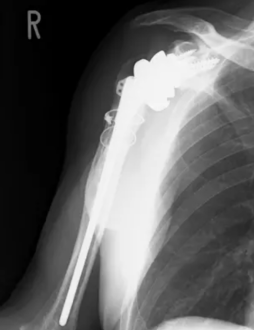

This is a different patient.

This patient did not receive an allograft.

If the bone split is small, the humeral split can close adequately without using an allograft.